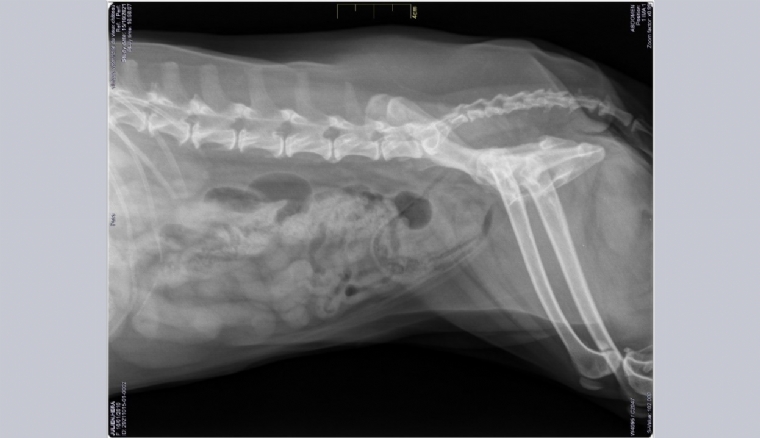

Mercredi 8 Mars 2023 Animaux de compagnieRadiographie abdominale de profil droit.

Une chienne cavalier king Charles de 11,5 ans est présentée pour de l'hématurie intermictionnelle. Elle a des antécédents de maladie valvulaire dégénérative stade B2 prise en charge médicalement et de pancréatite.